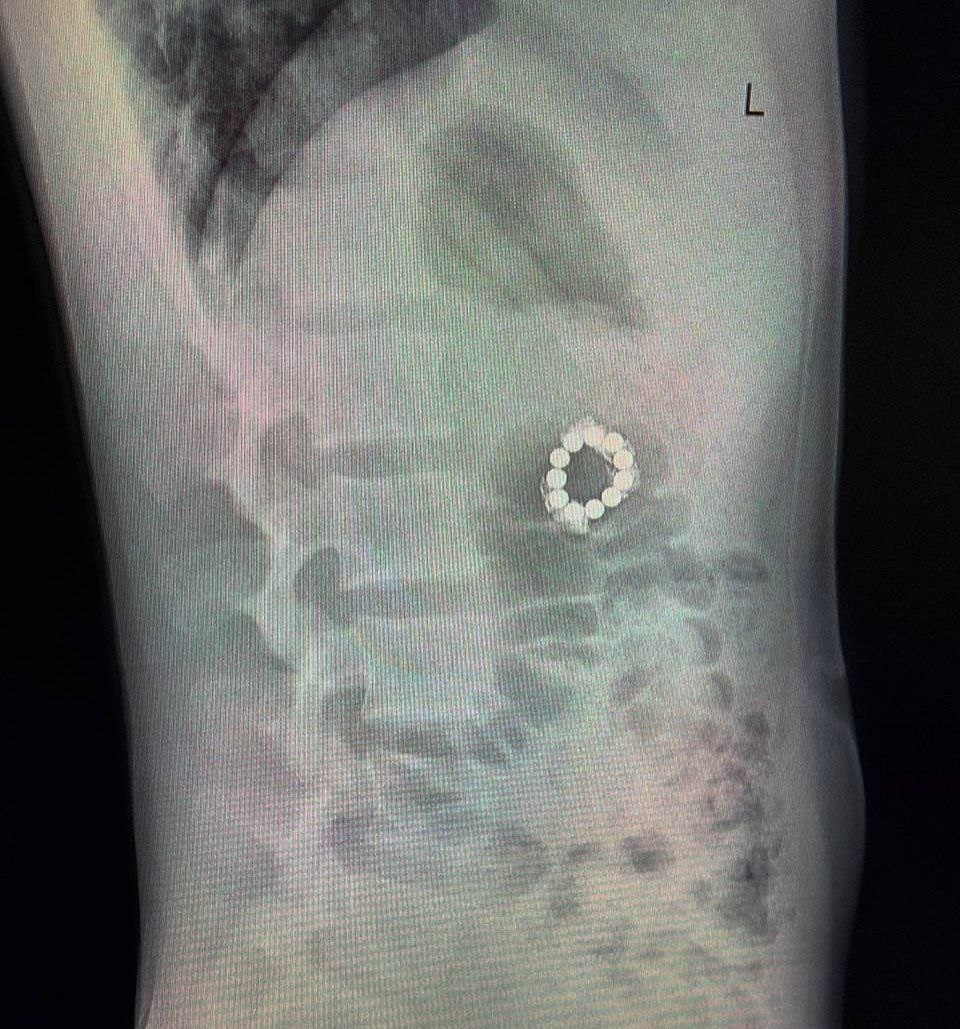

Ребёнок проглотил их из любопытства, но долго скрывал это от родителей из‑за стеснительности. Во время компьютерной томографии (проведённой из‑за боли в спине после тренировки по самбо) врачи обнаружили: 7 магнитов в желудке и 4 в других отделах ЖКТ. Магниты сцепились и вызвали перфорацию стенки желудка. В ходе операции эндоскописты извлекли магниты из желудка, а хирурги - из тонкой кишки. Мальчик успешно выписан домой, его жизни и здоровью ничего не угрожает.

Во время компьютерной томографии (проведённой из‑за боли в спине после тренировки по самбо) врачи обнаружили: 7 магнитов в желудке и 4 в других отделах ЖКТ. Магниты сцепились и вызвали перфорацию стенки желудка.

В ходе операции эндоскописты извлекли магниты из желудка, а хирурги - из тонкой кишки. Мальчик успешно выписан домой, его жизни и здоровью ничего не угрожает.